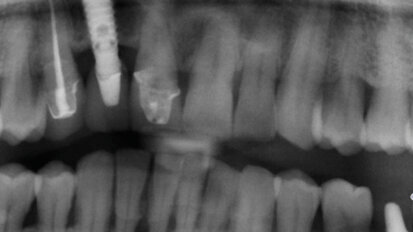

L’utilizzo della terapia fotodinamica HELBO nella parodontopatia

Un valido aiuto nel combattere il biofilm batterico, causa dei principali insuccessi nel trattamento sia della parodontite sia della perimplantite, viene ...